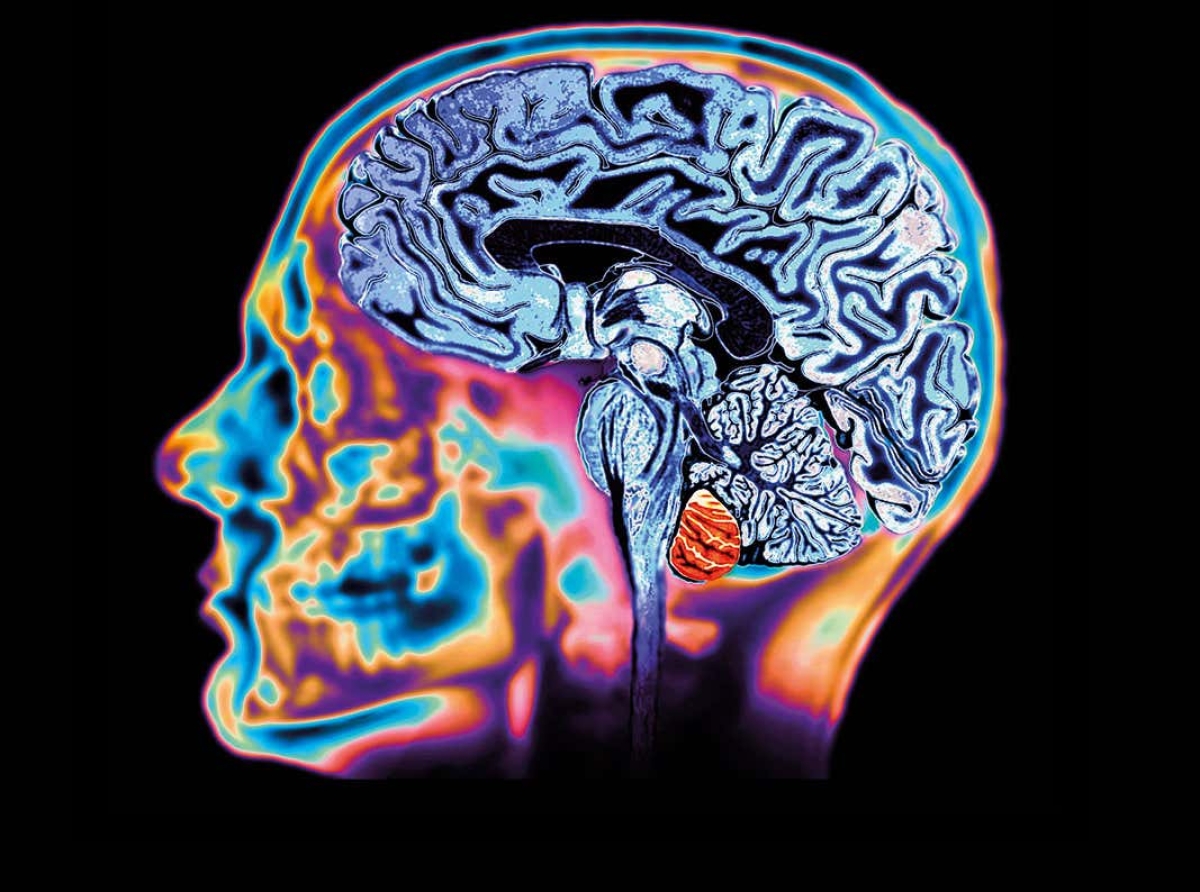

Algunas personas que han tenido experiencias cercanas a la muerte han informado del fenómeno de la repetición de recuerdos pasados al morir. Pero ésta es la primera prueba científica de que este "destello" puede ser real. Sin embargo, al tratarse de un estudio de caso único, es imposible hacer más suposiciones sobre la frecuencia del fenómeno o cómo puede ser la experiencia. Los investigadores hicieron el sorprendente descubrimiento en 2016, mientras estudiaban la actividad cerebral de un hombre canadiense de 87 años que había desarrollado epilepsia. El equipo estaba realizando un electroencefalograma (EEG), una prueba que detecta anomalías en la actividad eléctrica del cerebro, para comprender lo que ocurría durante sus convulsiones. Fue entonces cuando el hombre sufrió un repentino y fatal ataque al corazón. La inesperada muerte del paciente significó que el equipo había realizado, accidentalmente, la primera grabación de un cerebro moribundo.

En total, los investigadores registraron unos 900 segundos de actividad cerebral antes e inmediatamente después de la muerte del paciente. Esto les permitió observar con precisión cómo cambiaban sus oscilaciones neuronales, patrones repetitivos de actividad neuronal, también conocidos como ondas cerebrales, mientras moría. Descubrieron que en los 30 segundos anteriores y posteriores al paro de su corazón se produjo un cambio inusual en la actividad de sus ondas cerebrales. "Justo antes y después de que el corazón dejara de funcionar, ocurrieron cambios en una banda muy específica de oscilaciones neuronales", afirmó Ajmal Zemmar, investigador principal y neurocirujano de la Universidad de Toronto. Estos tipos específicos de oscilaciones se conocen como ondas gamma.